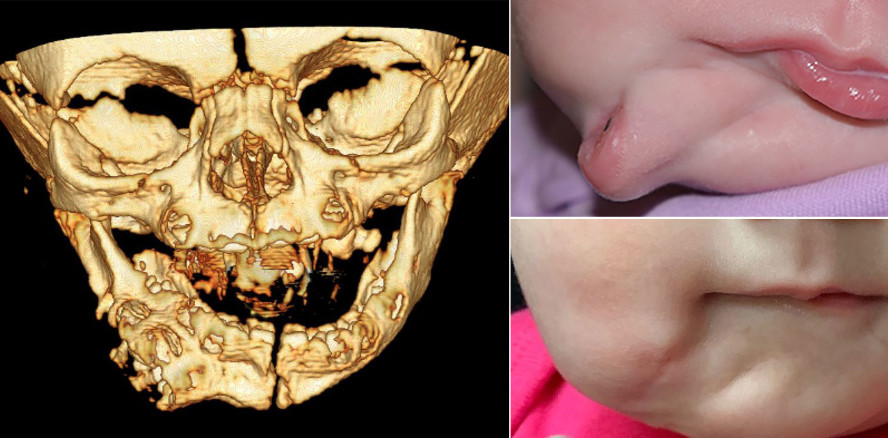

Zwei Augen, zwei Ohren, zwei Münder? Genau so kam ein Mädchen in Charleston, USA, zur Welt. Die extrem seltene Anomalie – bekannt als Diprosopus – konnte erfolgreich korrigiert werden. Für das Mädchen ist der Weg in ein „normales“ Leben damit frei.

Bereits in der 28. Schwangerschaftswoche war die Besonderheit im Gesicht aufgefallen. Allerdings waren die Ärzte davon ausgegangen, eine Zyste, im schlimmsten Fall einen Tumor zu sehen. Doch bei der Geburt wurde schnell klar, es handelt sich um einen zweiten vollständig ausgeprägten Mund – mit Lippen, Zunge und Zähnen. Er befand sich ca. einen Zentimeter unterhalb des „Hauptmundes“ und war rund 13 Zentimeter tief.

Glücklicherweise wies das Mädchen keine der mit dem Phänomen einhergehenden Komplikationen wie Hirn- oder Wirbelsäulenschäden auf. Zudem waren die beiden Münder nicht miteinander verbunden, sodass sie ohne Beeinträchtigung atmen, essen und trinken konnte.

Als sie das Alter von einem halben Jahr erreicht hatte, wurde der zweite Mund operativ entfernt. Die OP verlief erfolgreich, bereits weitere sechs Monate später erinnert lediglich eine kleine Narbe an die Verdopplungs-Anomalie. Die einzige Nebenwirkung sind einige nicht intakte Muskeln auf der rechten Gesichtshälfte.

Dieser außergewöhnliche Fall wurde in der Zeitschrift BMJ Case Report veröffentlicht. Bis heute sind nur 35 Fälle dieser Art bekannt.